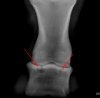

Ну вообще-то полость и дырка -- понятия похожие. Если киста в мягких тканях, она может быть заполнена жидкостью или гноем. А если в кости, то это дырка. Она и выглядит как дырка. Дырки в сыре видели? Очень похожая картина.

Вложения

• 1154_Missuria_3.jpg

1154_Missuria_3.jpg

42 KB · Просмотры: 2,261

• 1154_Missuria_2.jpg

1154_Missuria_2.jpg

42.6 KB · Просмотры: 1,955

Снимок на руках! Вот так это все выглядит:

fOrtuna, да, похоже, что это она, причем довольно большая. А другой проекции, вида спереди, нет? Такая проекция позволит точнее определить форму, размеры и расположение кисты.